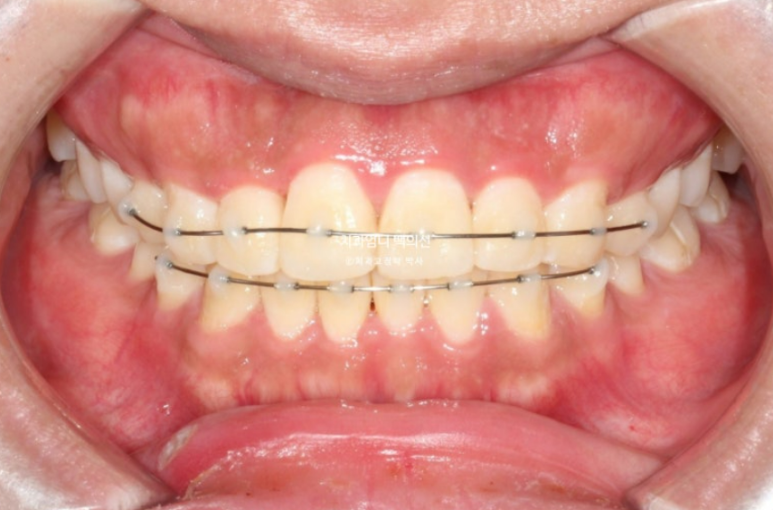

MTA 부분교정을 제1소구치부터 제1소구치까지 위 아래 8개씩 부착하여 치료를 시작했습니다.

치료시작 4개월째 모습입니다.

배열이 거의 완료되었습니다.